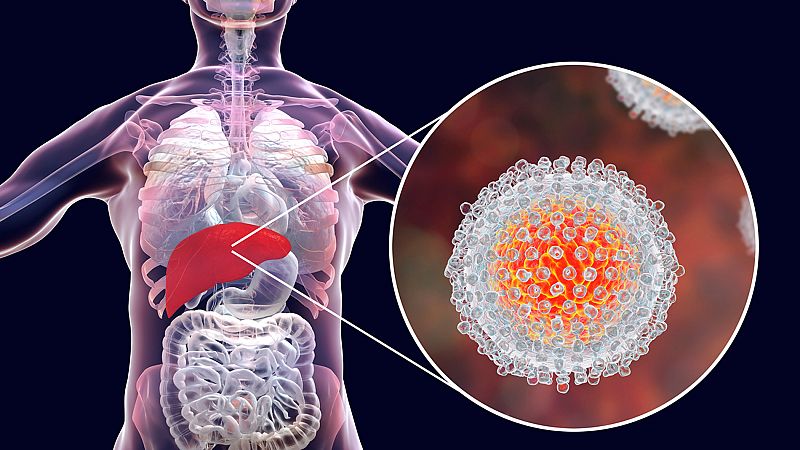

Hace unos años la hepatitis C no tenía cura y mataba a millones de personas. Hoy existe un tratamiento eficaz que permite pensar en su eliminación a medio plazo. La medicina consiguió erradicar la viruela, tiene arrinconada a la polio y, con vacunas y medicamentos, confía en acabar con otras enfermedades en las próximas décadas.

El objetivo de la Organización Mundial de la Salud (OMS) es erradicarla para el 2030, pero España lo lograría en apenas cinco años. Hay cinco tipo de virus que provocan inflamación hepática, algunas leves que remiten sin dejar secuelas, otras crónicas e incluso pueden ser letales. El tipo C es una infección, además, asintomática.